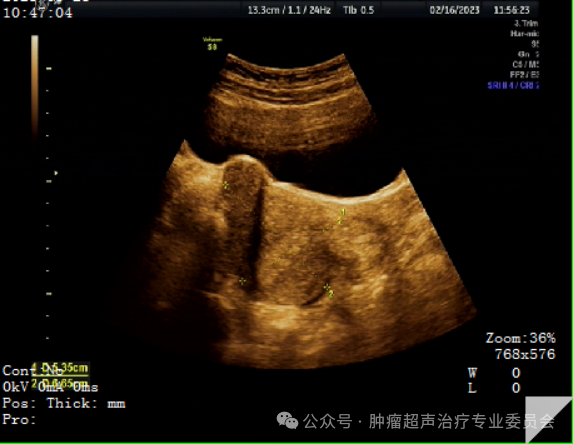

HIFU治疗后即刻子宫造影

子宫前后壁肌瘤的消融面积均达80%以上